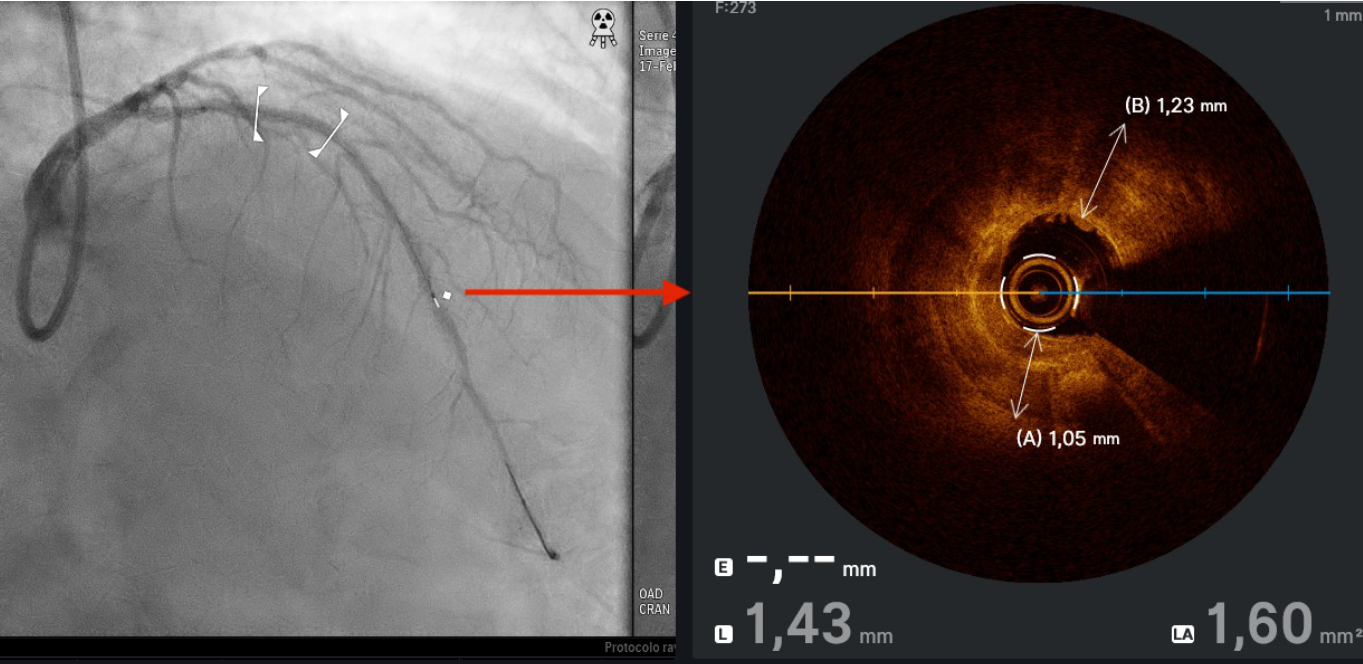

A 73-year-old man was hospitalized with acute coronary syndrome. Angiography showed severely calcified disease in the anterior descending artery and severe stenosis in the proximal, medial, and distal segments (Figure 1). Angioplasty was performed with an NC Trek Neo balloon (Abbott) with proper preparation of the plaque in the proximal and medial segments. Optical coherence tomography showed calcified plaque with a 360° ring and 1.2-mm thickness in the distal segment (Figure 2). Expansion attempts using a super high-pressure 2.5 x 10-mm OPN NC percutaneous transluminal coronary angioplasty (PTCA) balloon (SIS Medical) failed to fracture the calcification; rotational atherectomy with a Rotablator (Boston Scientific) was also unsuccessful. A 1.4-mm excimer laser coronary atherectomy catheter (Spectranetics) was also used (Figure 3) without fracturing the calcification, even after attempts with a super high-pressure balloon at 45 to 50 atm and being inflated for 40 to 60 seconds (Figure 4). Finally, a 3 x 28-mm Angiolite sirolimus-eluting stent (iVascular) was deployed in the proximal segments, followed by a 2.5 x 35-mm paclitaxel-eluting balloon (Medtronic) in the medial segment.